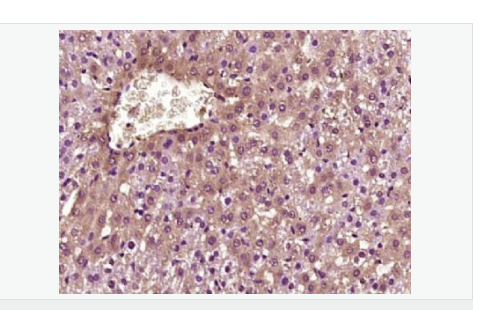

產(chǎn)品應用ELISA=1:5000-10000 IHC-P=1:100-500 IHC-F=1:100-500 IF=1:100-500 (石蠟切片需做抗原修復)

image.png